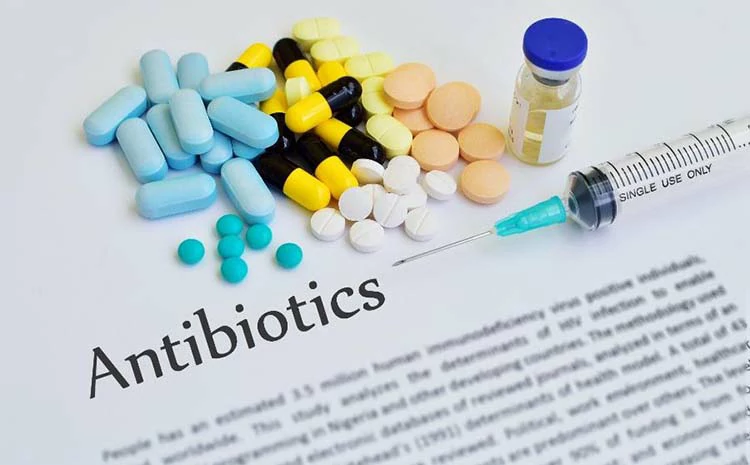

أفضل مضاد حيوي لعلاج الخراج الأسنان

المضادات الحيوية هي إحدى طرق العلاجات المكملة التي يوصي بها الطبيب في العديد من الحالات، لذا، من الطبيعي أن يتساءل العديد من المرضى عن أفضل مضاد حيوي لـ علاج خراج الاسنان.

استخدام المضاد الحيوي ليس أمرًا واجبًا في علاج خراج الاسنان، ففي بعض أنواع الخراجات غير المعقدة، قد لا تكون هناك ضرورة لاستخدام المضادات الحيوية، ويصف الأطباء المضادات الحيوية في حالات محددة وهي:

- إذا كانت العدوى شديدة أو منتشرة.

- إذا لم يكن من الممكن تصريف الخراج

من أهم المضادات الحيوية الموصوفة عادًة مع خراجات الأسنان ما يلي:

- الاموكسيسيللين وكلافولانيك أسيد وهو أفضل أنواع المضادات الحيوية التي يتم استخدامها في هذه الحالة.

- البنسلين، هو المضاد الحيوي المعتاد المستخدم لعلاج الالتهابات الخفيفة أو المتوسطة.

- الأزيثروميسين.

- السيفوكسين.

- الكليندامايسين.

- الميترونيدازول.